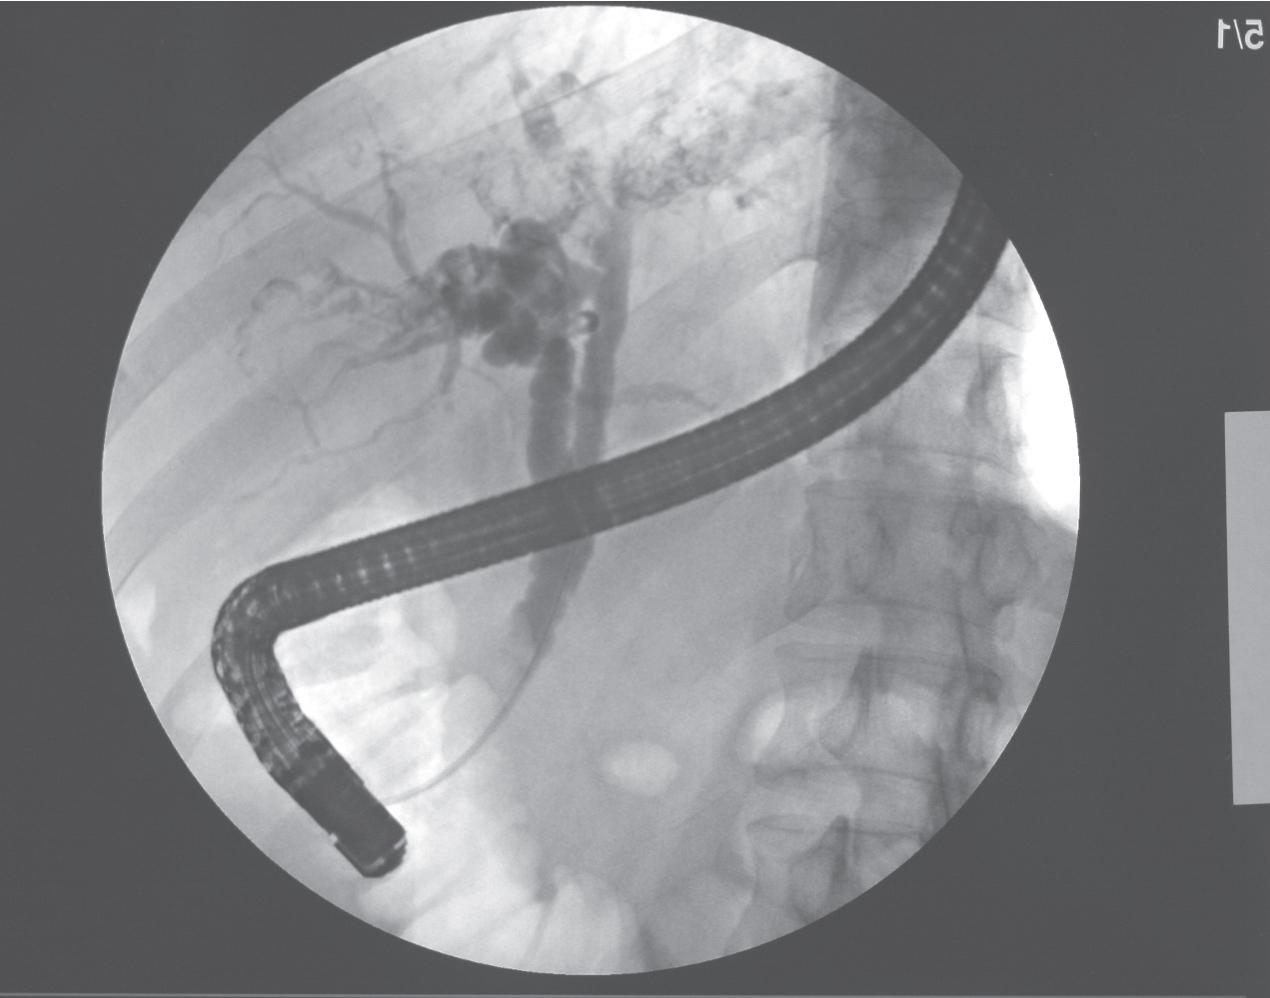

The presence of stones is a common finding in patients with RPC. Whether stones or stricture formation develop first remains uncertain. The stones act as a nidus and promote bacterial colonization and infection. Repeated infections are associated with strictures of the biliary system, thereby hindering bile flow, which may further promote stone formation and recurring infection. Endoscopic retrograde cholangiography (ERCP) findings of RPC patients commonly show a ductal stricture followed by clusters of stones. Patients can also develop cholangitis with focal strictures of the biliary system without any obvious stone. Other typical findings at ERCP include multiple stones and dilatation of the bile duct without any obvious stricture. In patients with intrahepatic duct strictures, there can be stone impaction causing a stone cast. The biliary strictures may not be severe, but even a mild narrowing can be sufficient to reduce the normal passage of bile promoting viscous bile and sludge formation as well as early precipitation of bile before discernible stones are formed.

FIGURE 44.1, Endoscopic retrograde cholangiopancreatography showing typical feature of recurrent pyogenic cholangitis with dilated common bile duct (CBD), CBD stone, dilated left intrahepatic duct, and arrowhead stricture of right intrahepatic ducts (see Chapter 30 ).

Ultrasound and CT are complementary examinations to cholangiography, which provides clear delineation of the ductal anatomy (see Chapters 16 , 30 , and 31 ). The patterns of ductal disease can be so diverse in RPC that detailed delineation of the entire biliary tract is essential. ERCP and percutaneous transhepatic cholangiography (PTC) are the direct cholangiographic methods of choice for RPC, which are both diagnostic and therapeutic. Our initial investigation of choice is ERCP for patients without previous hepaticojejunostomy, because the extrahepatic ducts, which are affected in more than 50% of patients with RPC, are better visualized ( Fig. 44.12 ). Additionally, repeated procedures can be performed with ease because blockages of previously placed internal biliary stents can be managed endoscopically. PTC is preferred when there has been a hepaticojejunostomy or choledochojejunostomy and when a stone or stricture located at the biliary confluence prevents filling of the intrahepatic ducts (see Chapter 31 ). PTC is also preferred when there is a peripheral stricture that ERCP may not be able to diagnose. One advantage of PTC is that it can be targeted to a particular segment. CT or US-guided percutaneous puncture of the targeted bile ducts have been shown to be very safe ( Fig. 44.13 A,B). When interpreting cholangiograms of patients with RPC, care should be exercised in looking for missing segmental ducts, especially with a paucity of intrahepatic filling; however, in case of sepsis, a complete cholangiogram may be risky because hepaticovenous reflux secondary to excessive contrast filling the entire biliary tree may worsen the septicemia ( Fig. 44.14 A,B). Correlation of cholangiography with US or CT can yield useful information in defining the cause of repeated attacks of cholangitis in patients who have seemingly cleared all stones.

FIGURE 44.12, This patient suffered from acute cholangitis from recurrent pyogenic cholangitis with initial cholangiogram showing a dilated common bile duct and a large obstructing stone (red arrow) (see Chapter 30 ).